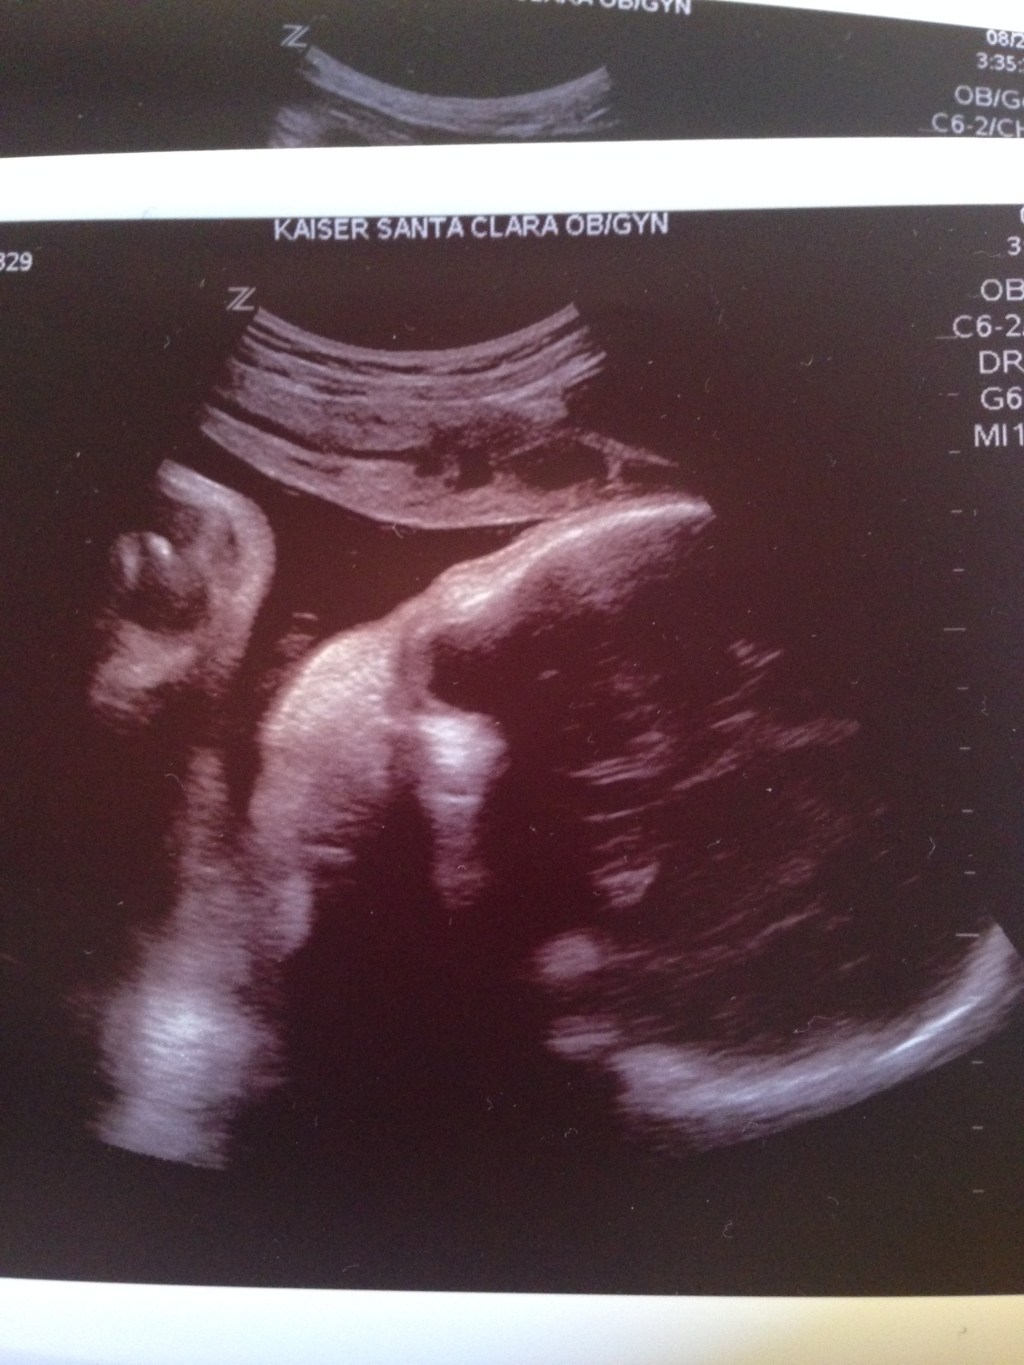

Nathan and I are taking the next month to write about our son Keller.

We will celebrate 1 entire year since he was born into Heaven on September 15, 2015.

There have been several times along this journey that I have used the phrase “my love song to Keller”. This is just a part of that song. I pray my entire life becomes a love song. A love song to our son. A love song that honors his short and beautiful life. A love song that surrounds his life with goodness and light, rather than darkness and bitterness. A love song to our overcomer Jesus Christ. A love song to the One who makes beautiful things out of the dust. A love song to the ONLY One who can make beautiful things out of us.

Each day we will share a piece of Keller’s life. We want to mourn, laugh, worship, and celebrate with you – our dearest friends – and with you – the ones whom the Spirit led to this space because you needed to know you aren’t alone and there is indeed Good News.